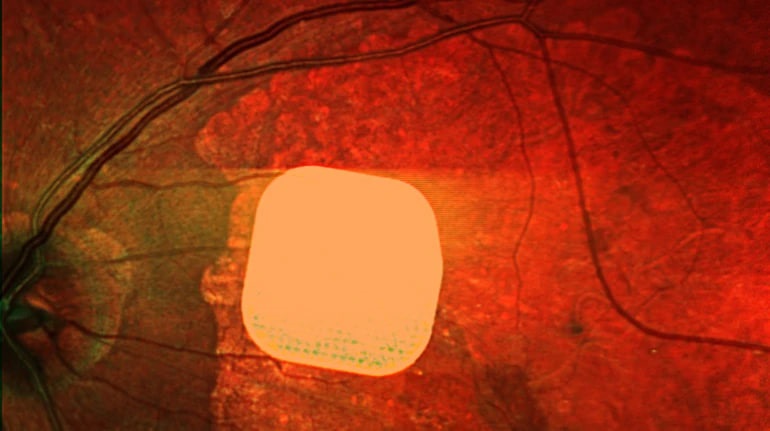

Британські лікарі зробили важливий крок у боротьбі з віковою сліпотою, випробувавши новий електронний імплант Prima, який допомагає пацієнтам із макулодистрофією, основною причиною втрати зору після 50 років, частково відновити зір. Мікрочип розміром лише 2×2 міліметри хірургічно встановлюють під сітківку ока, а пацієнтові також під’єднують систему окулярів доповненої реальності для передачі зображення на мікрочип. Дослідження, в якому взяли участь 38 пацієнтів, показало, що після операції 84% учасників знову змогли розрізняти літери, цифри та слова, хоча для користування цим видом зору потрібно навчитися. Лікарі вважають, що імплант Prima відкриває нові можливості для людей із важкими зоровими порушеннями, допомагаючи покращити їх якість життя.